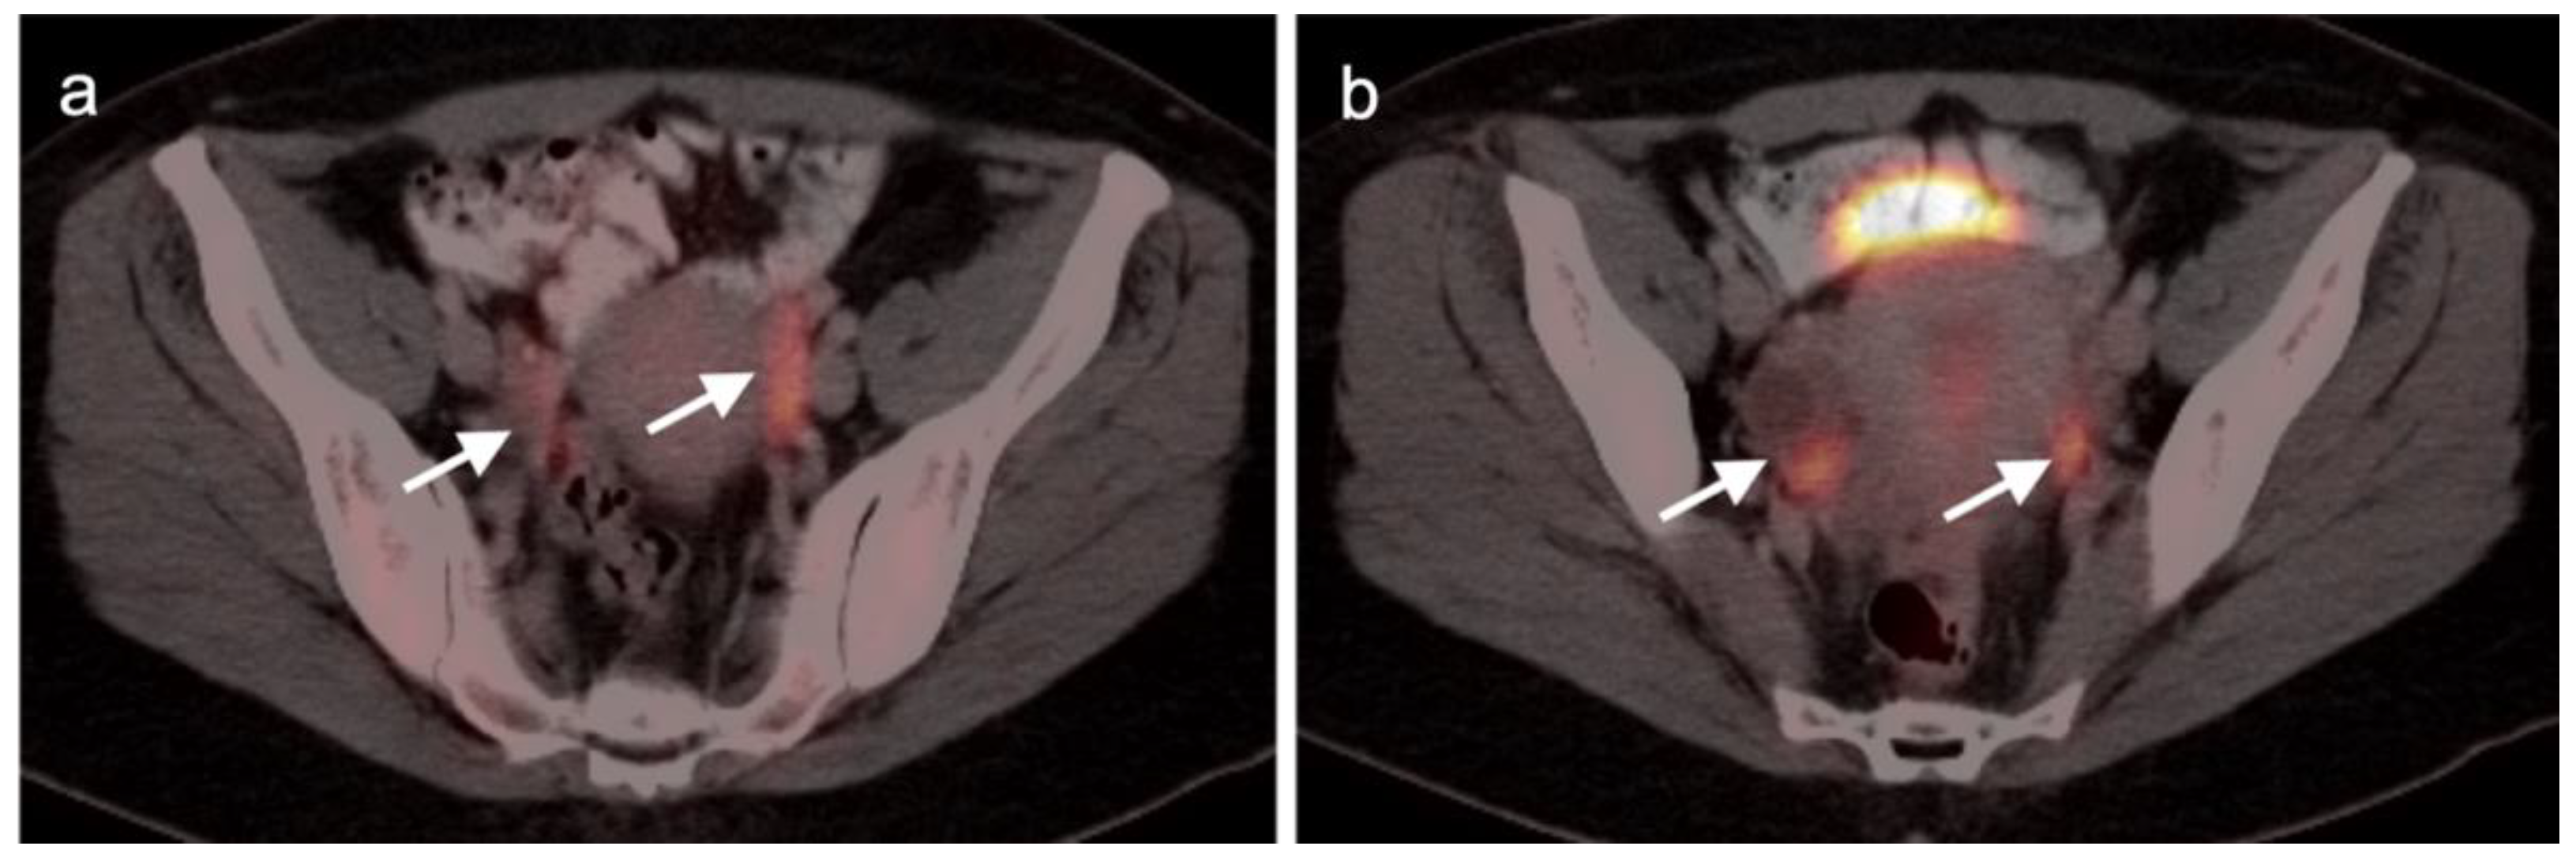

2.6. Vulvar Carcinoma